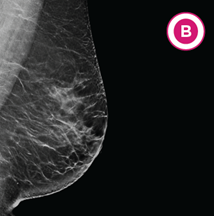

B. Scattered areas of fibroglandular (fi-bro-glan-juh-ler) density: